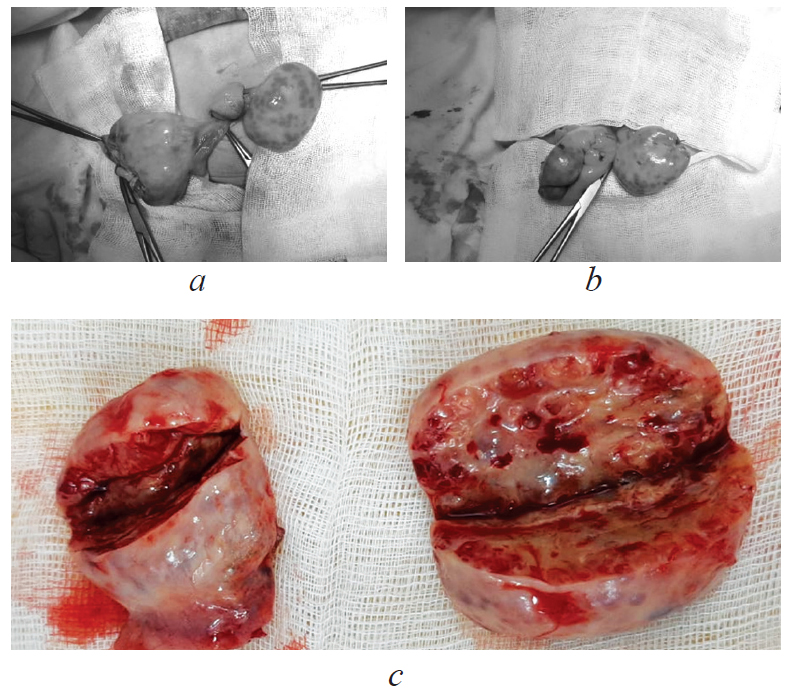

The ovaries measured 4.4 × 3.5 × 2.5 cm on the right and 5.2 × 4.5 × 1.5 cm on the left. On the incision in both ovaries, multiple cysts, with a maximum size of 0.5 × 0.4 cm, were revealed. The histological examination determined multiple follicular cysts lined with multi-row follicular epithelium with pronounced cell proliferation, dystrophic changes, and luteinization phenomena. A wide layer of large theca cells was adjacent to the follicular cysts. The identified morphological changes corresponded to secondary hyperthecosis (Fig. 4).

Fig. 4. Micropreparation. Ovarian tissue: а — staining hematoxylin-eosin. Magnification ×25. Big and small follicular cysts (arrows), the wall is formed by fibrous connective tissue; b — staining hematoxylin-eosin. Magnification ×40. Big and small follicular cysts (arrow), the wall is formed by fibrous connective tissue; c — staining hematoxylin-eosin. Magnification ×20. Cysts with luteinization, theca cells (arrows); d — staining hematoxylin-eosin. Magnification ×40. Cysts with luteinization, theca cells (arrow); e — staining: alcyan blue. Magnification ×40. Big and small follicular cysts (arrows), the wall is formed by fibrous connective tissue; the lining of cysts is formed by multinuclear follicular epithelium; f — staining alcyan blue. Magnification ×40. Big and small follicular cysts (arrows), the wall is formed by fibrous connective tissue; the cyst lumen has basophilic alcyan-positive content

Рис. 4. Микропрепарат. Ткань яичника: а — окраска гематоксилином и эозином. Ув. ×25. Крупные и мелкие фолликулярные кисты (стрелки), стенка представлена волокнистой соединительной тканью; b — окраска гематоксилином и эозином. Ув. ×40. Крупные и мелкие фолликулярные кисты (стрелка), стенка представлена волокнистой соединительной тканью; c — окраска гематоксилином и эозином. Ув. ×20. Кисты с явлениями лютеинизации, тека-клетки (стрелки); d — окраска гематоксилином и эозином. Ув. ×40. Кисты с явлениями лютеинизации, тека-клетки (стрелка); e — окраска альциановым синим. Ув. ×40. Крупные и мелкие фолликулярные кисты (стрелки), стенка представлена волокнистой соединительной тканью; выстилка кист представлена многорядным фолликулярным эпителием; f — окраска альциановым синим. Ув. ×40. Крупные и мелкие фолликулярные кисты (стрелки), стенка представлена волокнистой соединительной тканью; в просветах кист базофильное альциан-позитивное содержимое